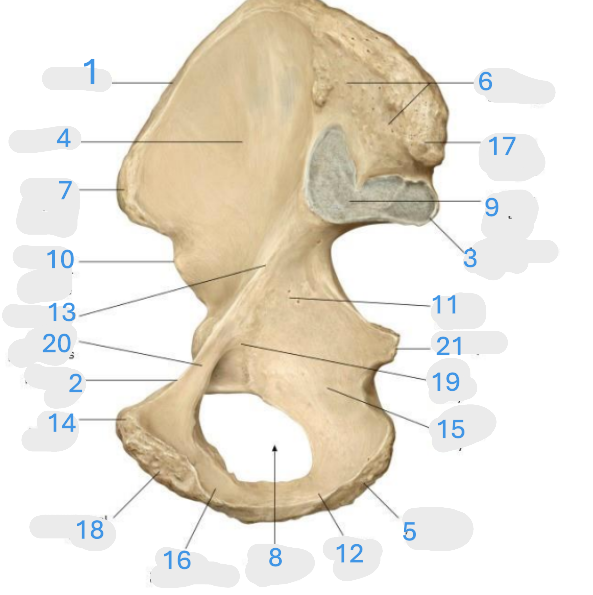

Where is the iliac crest

1

Where is the pectineal line

2

Where is the posterior iliac spine

3

Where is the iliac fossa

4

Where is the ischial tuberosity

5

Where is the iliac tuberosity

6

Where is the anterior superior iliac spine

7

Where is the obturator foramen

8

Where is the auricular surface of the ilium

9

Where is the anterior inferior iliac spine

10

Where is the ilium body

11

Where is the ischial ramus

12

Where is the arcuate line

13

Where is the pubic tubercle

14

Where is the ischium body

15

Where is the inferior pubic ramus

16

Posterior superior iliac spine

17

Where is the symphyseal surface

18

Where is the pubis body

19

Where is the superior pubic ramus

20

Where is the ischium body

21